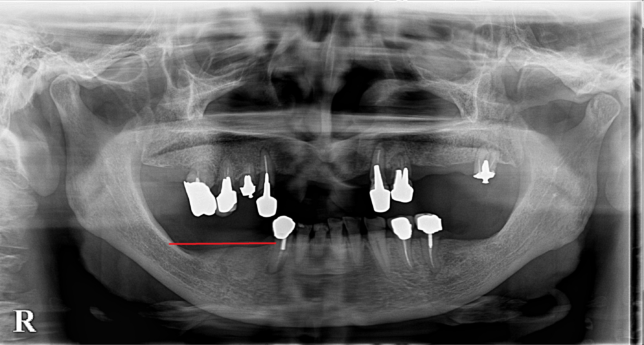

こちらのレントゲンをご覧ください。

7年前

赤い線より下部分の骨が痩せています。7年前より骨の高さが減っているのが分かるでしょうか?

痩せてしまう原因は嚙み合わせなど色々あるのですが、このように入れ歯を使っていても骨が痩せてしまうことがあるのです。